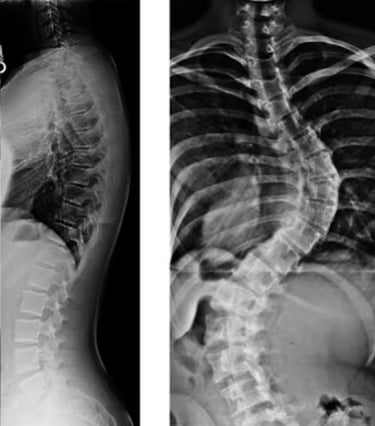

الجنف هو حالة بنيوية تصيب العمود الفقري، حيث ينحني العمود الفقري بشكل غير طبيعي من جانب إلى آخر، وغالبًا ما يصاحبه دوران حول محوره بدلًا من بقائه مستقيمًا عند النظر إليه من الخلف. وقد يأخذ هذا الانحناء شكل حرف S أو C، ويظهر الجنف بشكل أكثر شيوعًا خلال فترات النمو السريع مثل مرحلة المراهقة، إلا أنه قد يحدث في أي عمر.

في العمود الفقري السليم، تُشكِّل الفقرات عمودًا رأسيًا مع انحناءات طبيعية خفيفة من الأمام إلى الخلف. أمّا في حالة الجنف، فإن العمود الفقري ينحني أيضًا بشكل جانبي في المستوى الأمامي، وقد يصاحبه دوران، مما قد يؤدي إلى عدم التناسق في وضعية الجسم والمظهر العام.

ويُؤخَذ تشخيص الجنف عادةً بعين الاعتبار عندما يتجاوز انحناء العمود الفقري حدًا معيّنًا في الفحوصات التصويرية، وغالبًا ما يتم قياس ذلك باستخدام زاوية كوب (Cobb angle) في صور الأشعة السينية.

يبدأ تشخيص الجنف بتقييم سريري يشمل أخذ تاريخ صحي مفصّل وفحصًا بدنيًا شاملًا. وقد يلاحظ الممارس الصحي وجود عدم تماثل في مستوى الكتفين أو الوركين أو الخصر، أو اختلافًا في وضعية الجسم. وتُستخدم الفحوصات التصويرية، مثل الأشعة السينية، لتأكيد وجود الانحناء وقياس درجة شدّته.